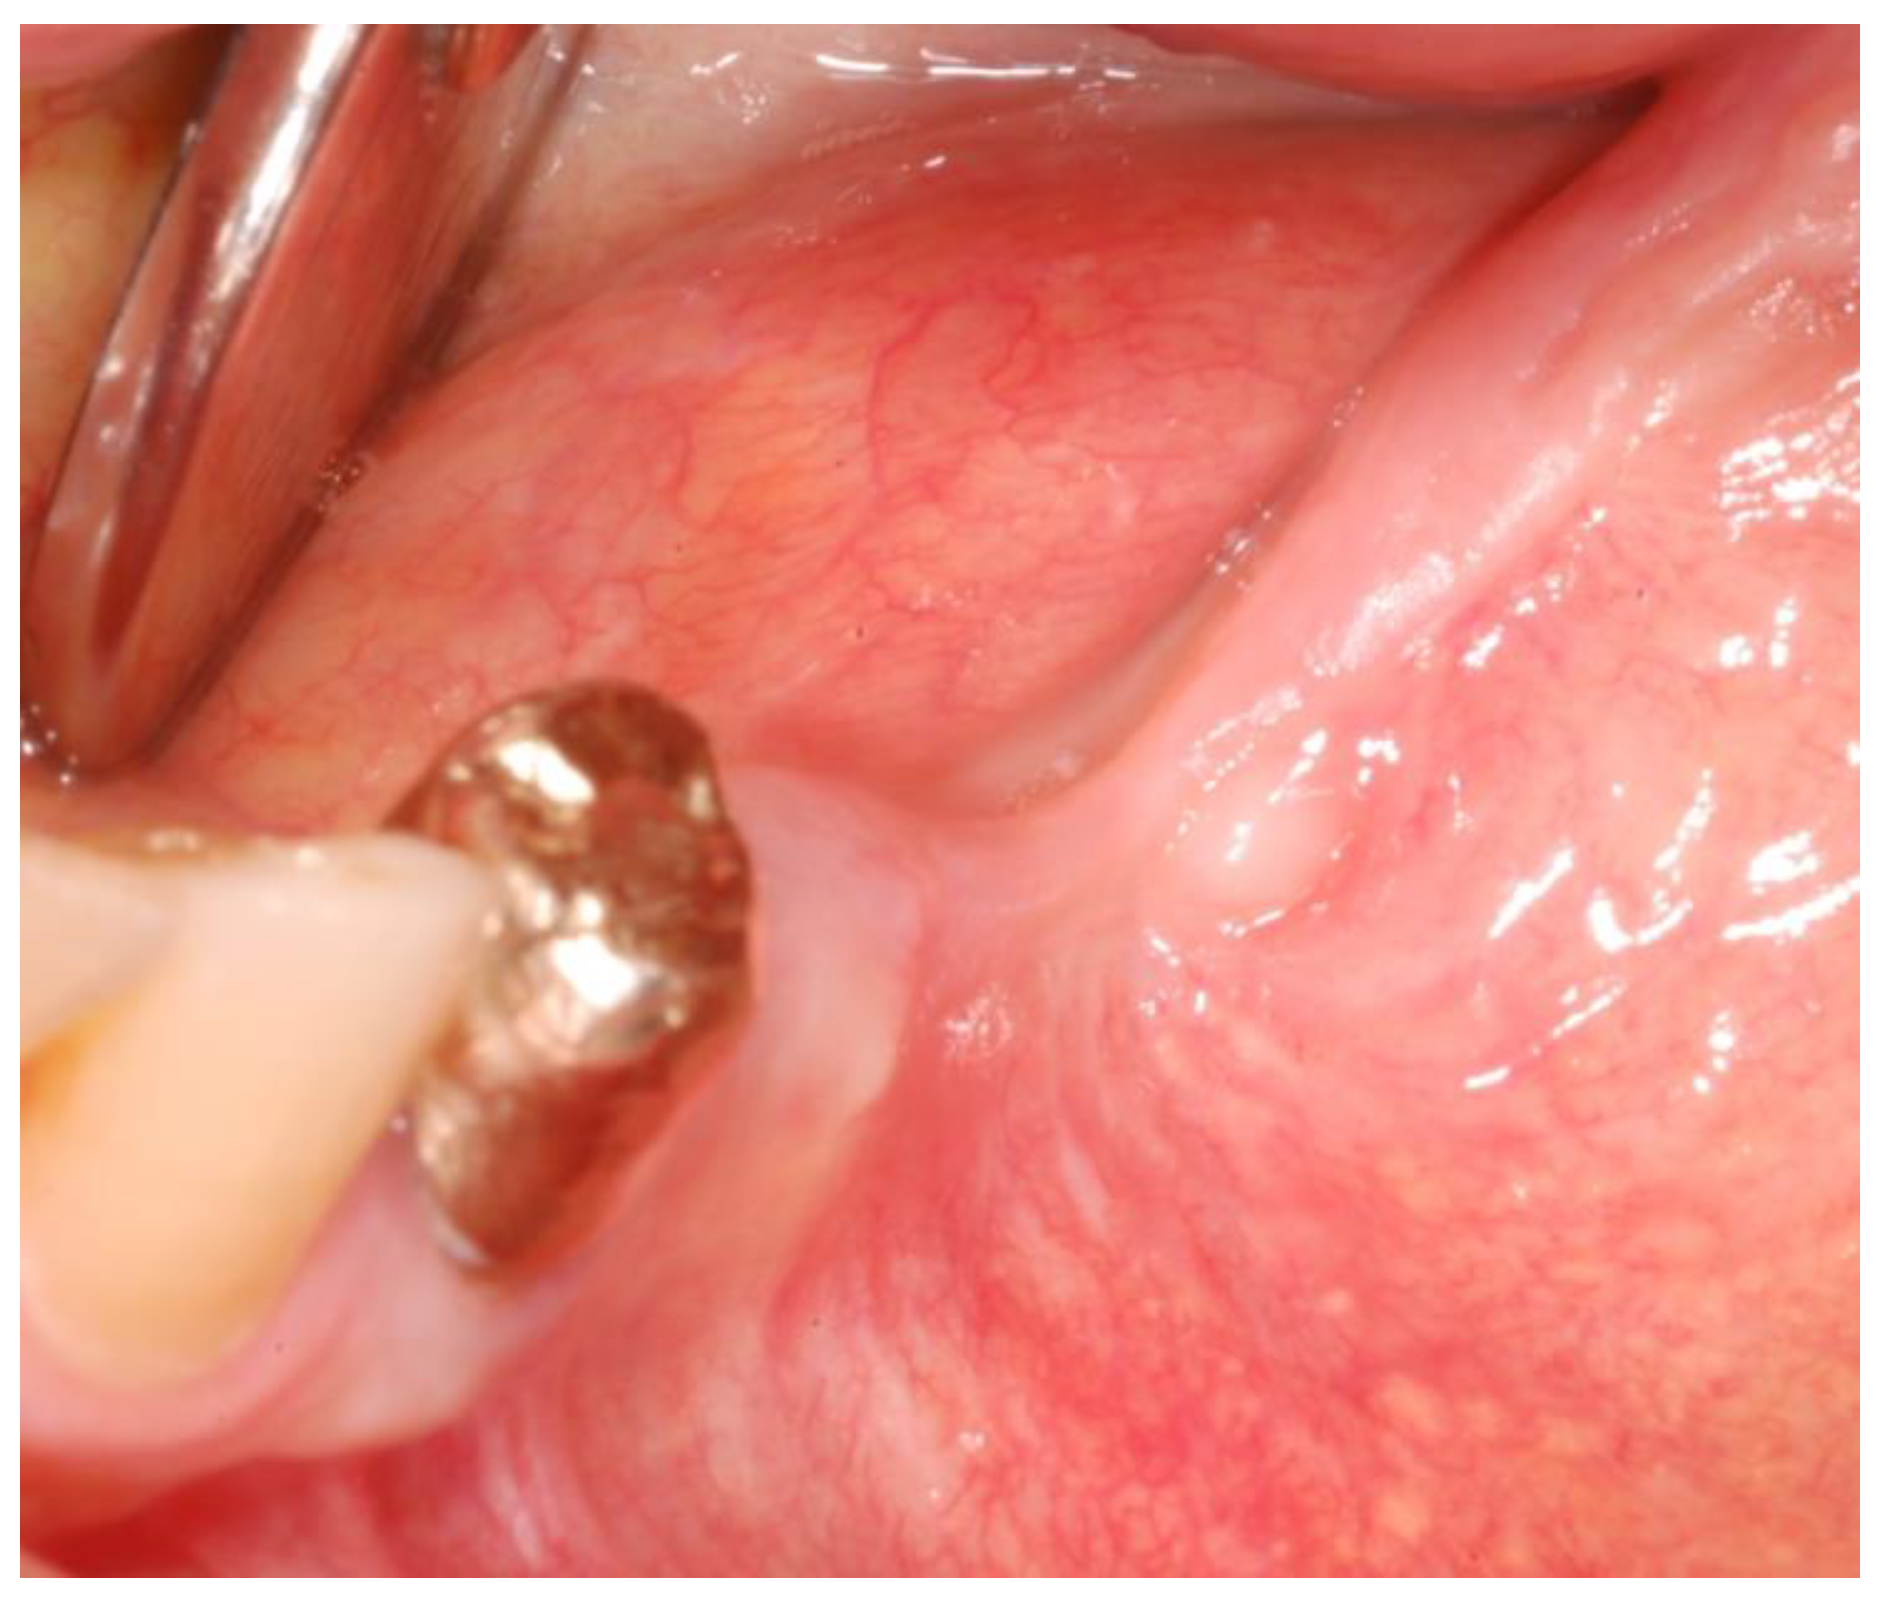

2.1. Case Presentation

- Surgery timing. The surgeon can follow in real time the ultrasonic tip position onto the system screen displaying the CBCT images and safely identify and remove the necrotic bone surrounding the inferior alveolar nerve on the right side.